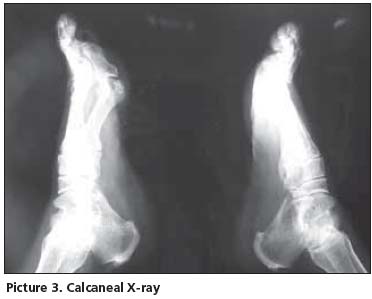

Her postero-anterior chest x-ray was evaluated as normal. In thoracic (Picture 1) and lumbosacral (Picture 2) graphs, marked squaring in her vertebras, shiny corners, symmetric syndesmophytes, bamboo spine, trolley track sign, osteoporosis and left faced scoliosis were observed. In pelvic x-ray her sacroiliac joints were normal. There were enthesopathic changes in the localization of the insertion of achilles tendon in calcaneus posterior bilaterally (picture 3). In magnetic resonance imaging (MRI) and conventional radiography, bilateral sacroiliac joints were regular and joints cartilage were normal (Picture 4,5). There were not any pathological signal changes in the bone surfaces that form the joints and the soft structures that were examined. Depending on the current clinical status and the radiography and imaging tests, the patient was defined as spondyloarthropathy (SpA).

Diagnosing axial SpA [Ankylosing Spondylitis (AS) and undifferentiated SpA(uSpA) with predominant axial involvement but without radiographic sacroiliitis] in the absence of radiographic sacroiliitis poses a major challenge to many physicians. In the absence of diagnostic criteria, classification criteria are often used to aid the diagnostic process in daily practice. The most often cited classification criteria for SpA are the Europian Spondylarthropathies Study Group (ESSG) criteria that were proposed in 1991. According to these criteria, in the absence of sacroiliitis; patients with inflammatory spinal pain or synovitis (asymmetric, predominantly in the lower limbs) in addition to any one of the following (positive family history, psoriasis, inflamatory bowel disease, alternate bottock pain, enthesopathy) are classified as seronegative SpA with 77% sensitivity and 89% specificity. In the presence of sacroiliitis, sensitivity is 86% and specificity is 87%[1]. However in a recent study from Spain, it was observed that the performance of the ESSG criteria as diagnostic criteria in daily practice was moderate: only 46.6% of patients with possible SpA who met the ESSG criteria at entry into the study were judged by their rheumatologist to have SpA after 5 years of follow up[2]. The typical radiographic changes of AS are seen primarily in the axial skeleton, especially in the sacroiliac, discovertebral, apophyseal, costovertebral, and costotransvers joints[3]. Syndesmophyits seen in AS and entheropathic arthiritis are usually symmetrical and bilateral, while that are seen in reactive arthiritis and psoriatic arthritis are nonmarginal, rough and asymmetrically located[4]. The radiological appearance of arthritic changes in sacroiliac joints has been regarded as a hallmark of AS according to Modified New York Criteria[5]. In AS patients in addition to sacroiliitis, arthritic changes in the spine visualized by x-ray develop in 57- 88% of the patients[6,7]. In literature, there were AS patients with typical clinical features but no radiological sacroiliitis[8]. Khan et al reported that radiographic sacroiliitis is frequent in AS but is not an early or obligate manifestation of the disease. In particular, relatives of AS with IBP may not show radiographic sacroiliitis even after long follow-up[9]. Rudwaleit reported that in a small proportion of AS patients may never develop radiolographic sacroiliitis despite having IBP for many years. SpA patients with predominantly axial symptoms should be considered as having a same disease entity as AS patients, independent from the presence of radiographic sacroiliitis[10]. In one study 60% of SpA patients had developed definite AS after 10 years of follow-up. It took an average of 9 years (+/-6 years) for radiological sacroiliitis to appear in these patients. A further 20% still had chronic uSpA and might have developed radiological sacroiliitis if their follow-up had been continued for a longer time[11]. Again in another family study, radiographic evidence of sacroiliitis was found in 40% of patients with a symptom duration of <10 years, 70% with symptoms for 10-19 years, and 86% with symptoms for ≥ 20 years[12]. The morphological changes used to assess spinal involvement in x-ray were syndesmophytes, shining corners, squaring, arthritis of the apophyseal joints, spondylodiscitis, bamboo spine and trolley track sign[13]. Descriptions of spinal x-ray changes typical of AS without concomitant radiological sacroiliitis are thus relatively uncommon. Besides, Moll reported that these spinal x-ray changes develop later in the course of AS and usually after radiological sacroiliitis is evident.[14]. MRI is considered to be very helpful in detecting signs of sacroiliitis that are not yet visible in x-ray[15]. Although our HLA B27 positive patient has been suffering from IBP for 10 years, no sacroiliitis was detected in her pelvic x-ray and MRI. However in her throracic and lomber x-ray, all radiological abnormalities such as squaring, shiny corner, syndesmophytes, bamboo spine, trolley track sign were clearly present. In her foot x-ray, bilateral calcaneal enthesopathy was detected.